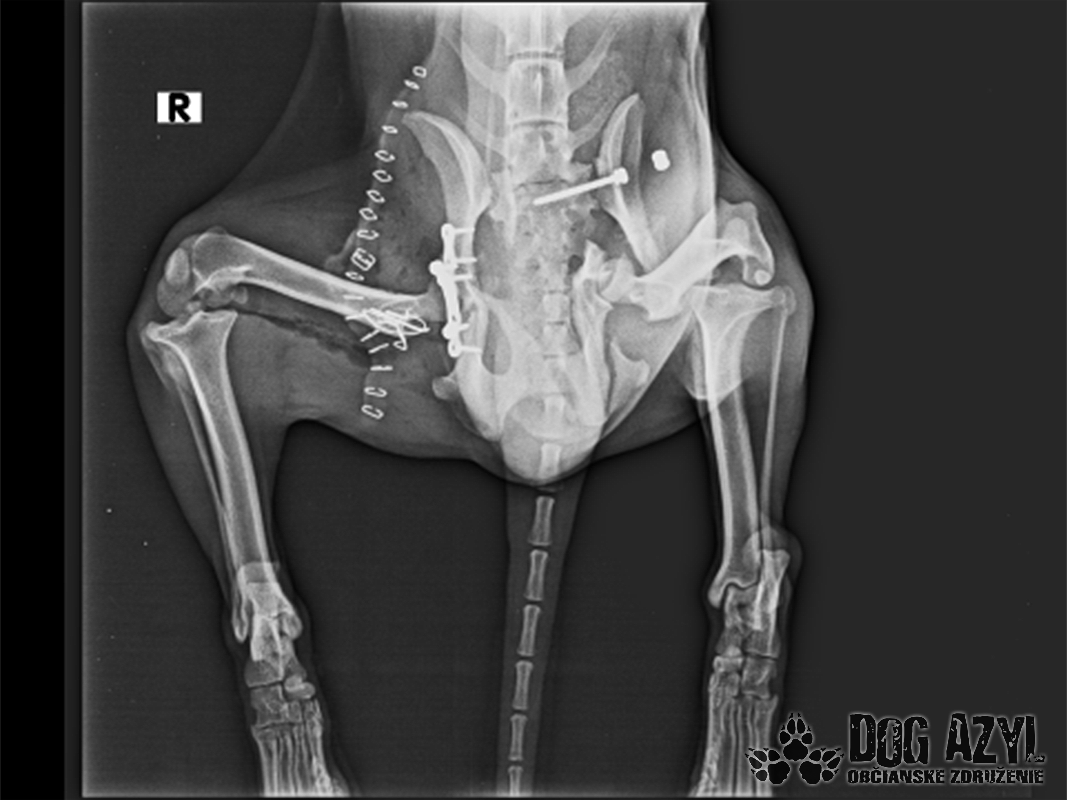

Vianoce nám klopú na dvere a mali by to byť sviatky radosti a pokoja. No u nás nebudú a pre malého Jamesa už vôbec nie. Malého Jamesa sme prijali s mnohonásobnými fraktúrami panvy. Presnejšie, s obojstrannou iliosakrálnou luxáciou/fraktúrou, viacnásobnou fraktúrou panvy, vrátane fraktúry kranialneho acetabula obojstranne. Áno, znie to hrozivo a keď si pozriete snímky z RTG, bude to ešte hrozivejšie (ďalšie snímky ešte doplníme).

Čakali ho teda štyri, veľmi náročné ortopedické operácie, takže sa musel trocha posilniť. Do starostlivosti si ho vzala MVDr. Panyi Terzieva a 17.11. mohol absolvovať prvú operáciu. V "prvom kole" krpec zvládal anestézu tak dobre, že sa rovno mohli spojiť dve operácie a tak sa celá ľavá strana dala do poriadku. Zostal samozrejme naďalej hospitalizovaný. Ďalší zákrok sa naplánoval na 20.11. a našťastie opäť všetko prebehlo hladko, a zoperovala sa celá pravá strana(nechceme sa dlho rozpisovať, prikladáme lekársku správu). James bol prepustený 24.11. ako chodiaci pacient a bez problémov ovládal aj vylučovanie! Je to priam zázrak, za ktorý opäť vďačíme MVDr. Vatolíkovi a jeho teamu.